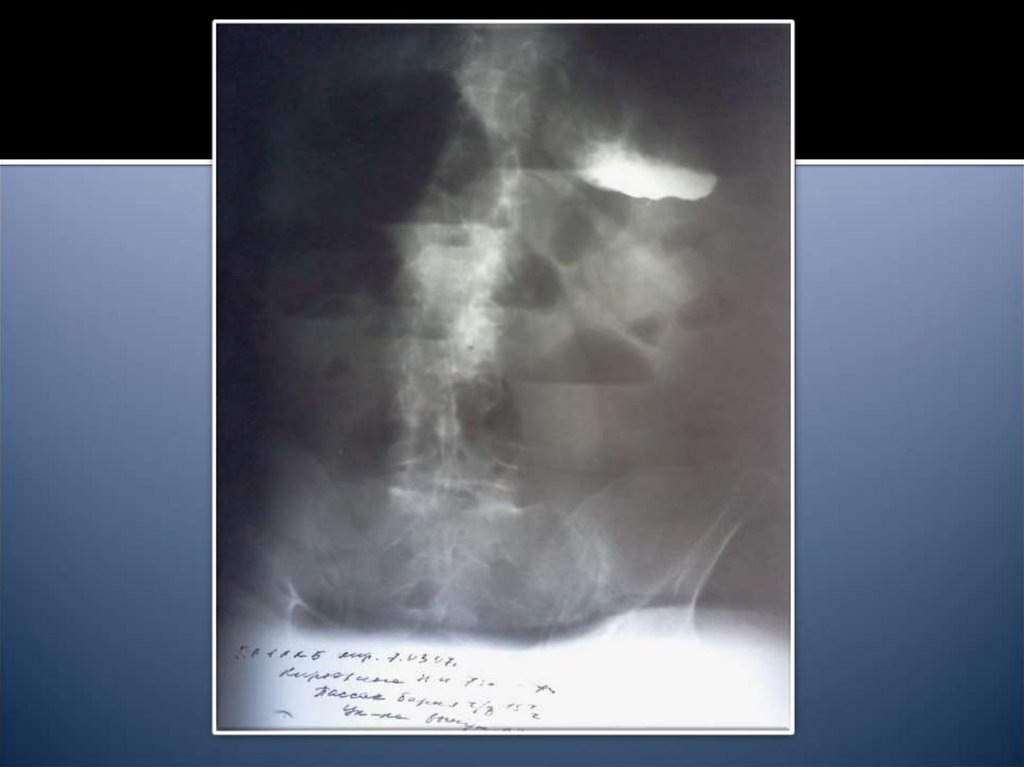

14. Рентгенологические признаки

Чаши Клойбера

Симптом Кивуля (аркады)

Проба Шварца

Пневматоз петель кишечника